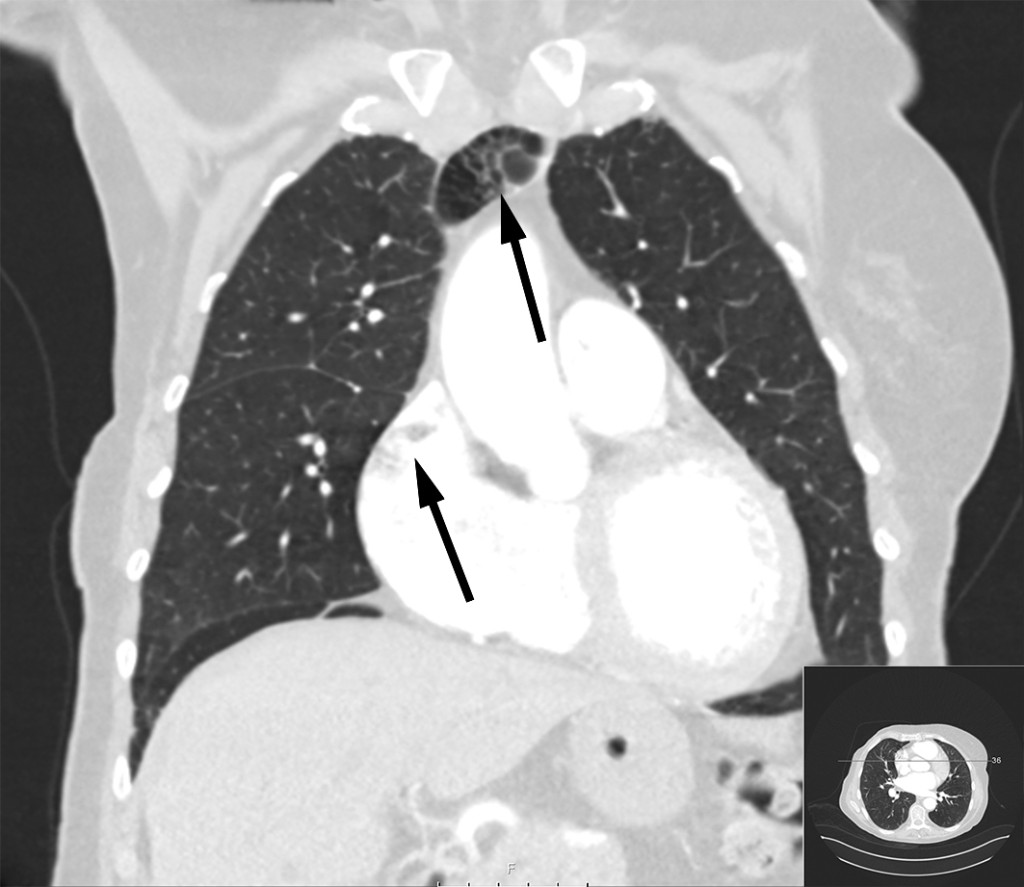

Bildene viser betydelige luftmengder i venesystemet hos en kvinne i 70-årene. Spesielt sees luft i venstre vena brachiocephalica, høyre forkammer og høyre ventrikkel. Grunnet mistanke om sternumfraktur var det rekvirert CT thorax med kontrast. En liten sternumfraktur ble funnet i tillegg til luftemboliene.

Sannsynligvis har det i forbindelse med kontrastundersøkelsen blitt injisert luft venøst. Vakthavende intensivlege ble varslet etter at radiolog hadde gransket bildene, og pasienten ble tilsett umiddelbart. Hun var respiratorisk og sirkulatorisk stabil, med lettgradig dyspné som eneste symptom. Hun ble leiret i venstre sideleie med hodet litt lavere enn kroppen (Durants manøver) og fikk ti liter oksygen på maske med reservoar. Dykkerlege ved Haukeland universitetssykehus ble kontaktet.

Pasienten ble liggende i venstre sideleie i åtte timer med samtidig oksygenbehandling. Deretter ble ny CT thorax gjennomført, og denne viste fullstendig resorpsjon av luftmassene. Pasienten ble så overført til sengepost for lindring av smerter fra sternumfrakturen.